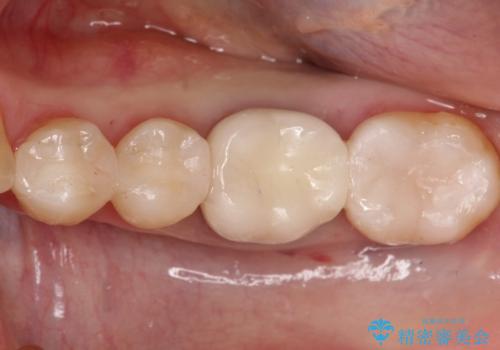

かかりつけ医にて応急的に修復してますが根本的な治療を希望され、矯正的挺出を行ったのち、歯周外科を行い、歯冠修復をしております。

歯肉縁下の水平破折をきちんと治療するためには時間も費用もかかります。